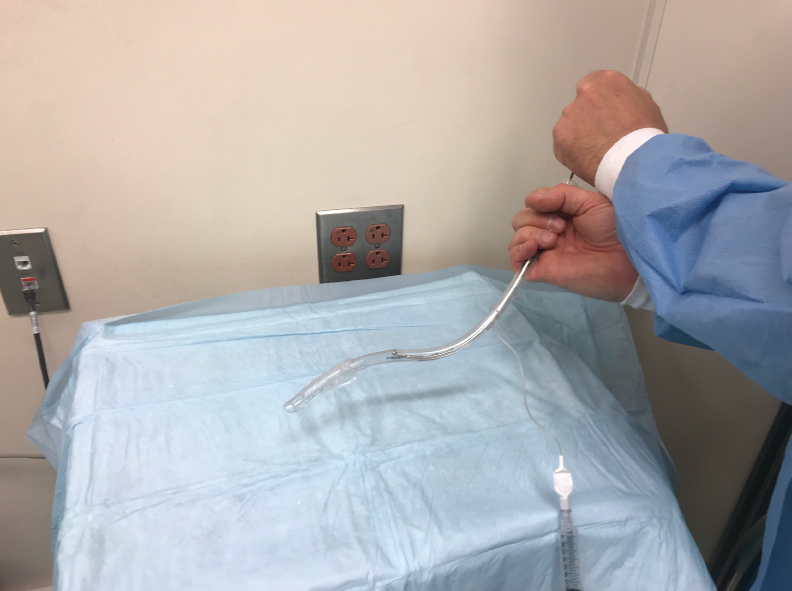

One of the inherent problems of VLs is that they allow the visualization of the cords by looking around the corner but they do not always allow for easy intubation because they do not line up the oral, laryngeal and pharyngeal axes as efficiently as a DL. This issue is particularly significant in patients with an anterior airway where the ETT first needs to ante-flex to enter the cords and then retro-flex to advance further into the trachea. This lack of aligning oral, laryngeal and pharyngeal axes during the use of a VL is probably the reason why a VL has not been found to be superior to a standard DL when used for routine intubation of patients without anterior airway [34,35]. During intubation with a VL the ETT will occasionally pass through the vocal cords but then stop advancing. This is especially likely when the patient has an anterior airway. The problem in this situation is that the tip of the ETT is lodged against the anterior wall of the trachea. In this case the ETT needs to retroflex after passing the vocal cords in order to line up with the axis of the trachea. In order to advance the ETT the stylet should be withdrawn 2-3 cm. An assistant should then hold the top of the stylet in place to stabilize it while the intubator is turning the ETT 180 degrees to the left in order to retroflex the tip of the ETT (Figure 2). This will align the axis of the ETT with that of the trachea and often allows for atraumatic advancement of the ETT into the trachea. ETTs should always be well lubricated whenever intubation difficulty is anticipated. Some practitioners reverse-load the ETT onto the VL stylet to achieve a similar effect.

Figure 2: Retro-flexion of the tip of the endotracheal tube (ETT) when it is turned 180 degrees while holding the top of the stylet in place.